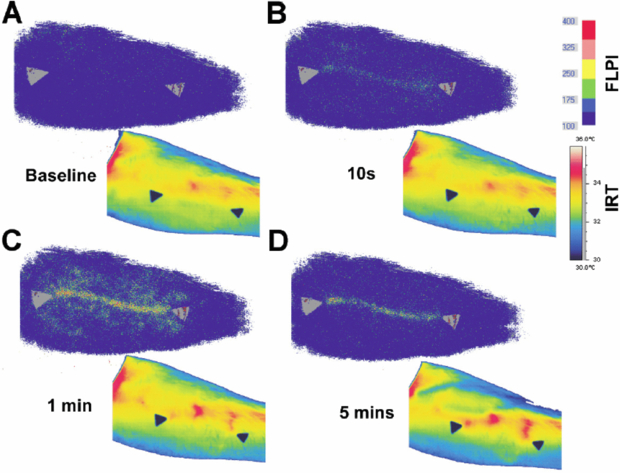

Figure 11. Nose blood flow versus temperature as ambient temperature is varied across the range 15–40 °C (permission granted to re-use from Mabuchi et al 1995 The Thermal Image in Medicine and Biology (Vienna: Uhlen)).

Download figure:

Standard image High-resolution imageAfter cold challenge of the hand, Pauling et al (2012b) found a good correlation in healthy subjects between thermography and hand skin perfusion as measured by the laser speckle contrast technique, and the correlation was strongest in glabrous skin. Buick et al (2009) also found a similarity between thermography and LSCI when measuring response to hand cold challenge at the fingertips. However the two techniques showed a different response to a skin scratch at the volar surface of the forearm: the speckle instrument revealed an inflammatory reaction at the scratch site, whereas thermography predominantly highlighted increased flow in nearby perforator vessels bringing blood flow to the scratch (figure 12).

Figure 12. Evolution of laser speckle contrast perfusion (upper images) and skin temperature (lower images) after a scratch to the volar surface of the forearm (permission granted to re-use from Buick et al 2009 Thermol. Int. 19 43–6).

Download figure:

Standard image High-resolution imageMerla et al (2007) formulated a heat-flow model through the skin and were able to convert a thermal image into an image estimating cutaneous blood flow (in arbitrary units) at each pixel point. These cutaneous blood flow estimates correlated well at the dorsum of the hand with blood perfusion as measured by LDPI (laser wavelength 670 nm). No data was presented for the correlation between the two methods specifically at the glabrous skin of the fingertips.